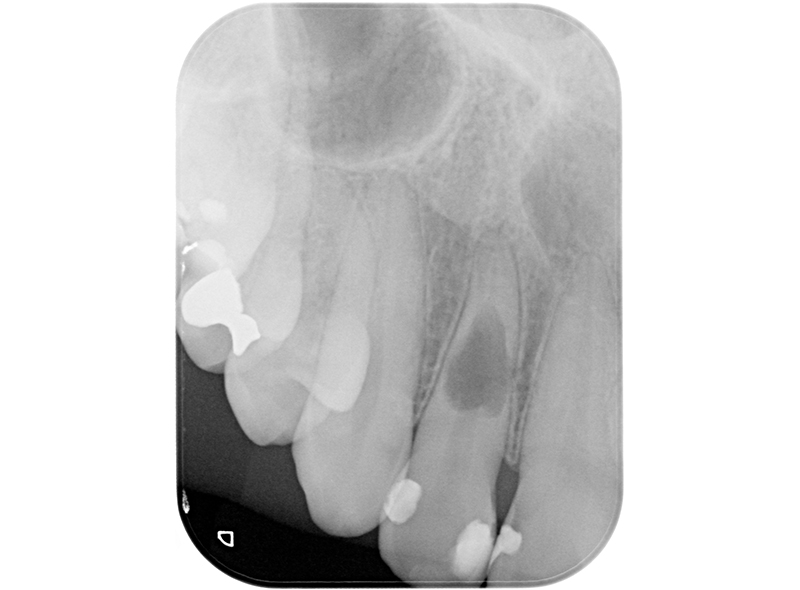

侵襲性歯頚部吸収・歯根吸収

Before

| 治療内容 | 6年前にサバイバルゲームでBB弾が歯に当たり、歯が欠けた。 歯髄診査では、11,21ともにEPT+、Cold+。11は侵襲性歯頚部吸収、21は内部の炎症性吸収と診断。また、11にはパーフォレーションも認めた。 21は根管治療、ダイレクトボンディングにて対応。 11は、歯冠部の審美に対してはダイレクトボンディングにて対応。 まず侵襲性歯頚部吸収による吸収部を粘膜剥離しバイオデンティンにて外部より封鎖。後日、パーフォレーション部をバイオデンティンにて根管内部よりリペア。歯髄は正常と診断したが、予防的に根管治療を行うこととした。歯冠部からのアクセスが困難だったため、逆根管治療(歯根端切除術)にて対応。 |